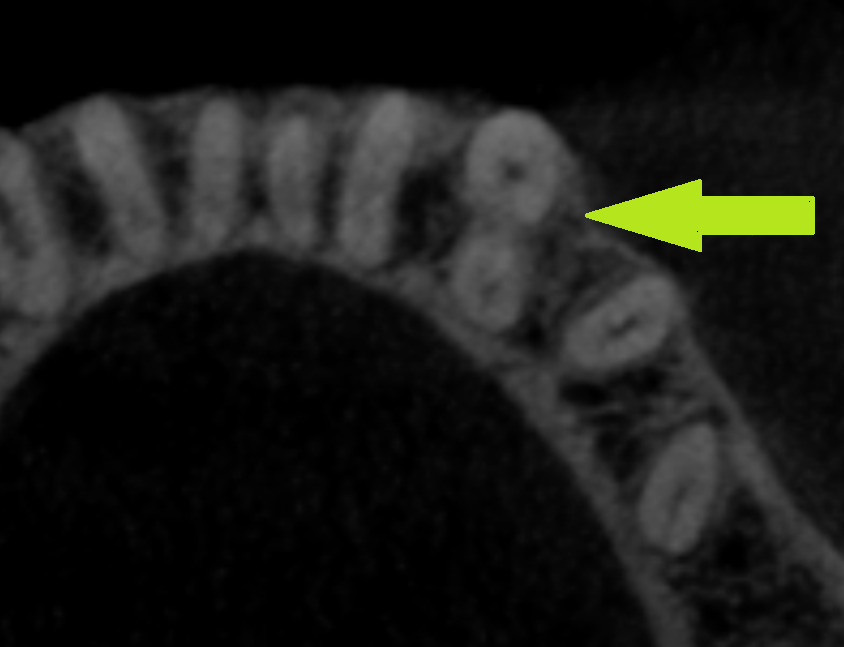

W tym miejscu należy wspomnieć, że zębami jednokorzeniowymi, które posiadają niemal zawsze jeden kanał są zęby przednie szczęki (ryc. 1). Zęby przednie żuchwy, mimo iż są zębami jednokorzeniowymi, bardzo często posiadają dwa kanały. Według badań przeprowadzonych w polskiej populacji dwukanałowe zęby sieczne występowały w 1/3 przypadków, a kły dolne w nieco ponad 10% (ryc. 2) (4). Również dość często dwa kanały można stwierdzić w jednokorzeniowych zębach przedtrzonowych (drugi ząb przedtrzonowy szczęki; zęby przedtrzonowe żuchwy) czy zębach trzonowych (np. w często występującym jednokorzeniowym drugim zębie trzonowym żuchwy). W przypadku tych zębów wykonanie zdjęcia wewnątrzustnego w projekcji skośnej uwidacznia obecność dwóch lub większej liczby kanałów, choć niekiedy (np. zęby sieczne dolne) obrazy zębów mogą na siebie nakładać się uniemożliwiając analizę zdjęcia pod kątem występowania odmiany dwukanałowej. W takim przypadku okazuje się przydatna tomografia komputerowa.

Ryc. 2. CBCT dwukanałowego kła dolnego (strzałka) – przekrój poprzeczny wykonany w części środkowej korzenia.